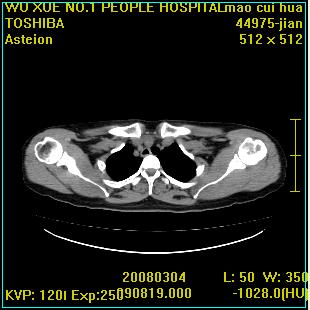

标题: CT12025:男,50岁,左肩活动受限半年。 [打印本页]

标题: CT12025:男,50岁,左肩活动受限半年。

肩关节骨质破坏呈小囊状,其周软组织轻度肿胀,余未见异常。

考虑:肩袖损伤。建议mri。

左侧肱骨头密度不均匀,高低混杂,周围软组织略肿胀,考虑结核性病变。

左侧肱骨头密度不均匀,高低混杂,髓腔密度稍高,周围软组织略肿胀,肌间隙模糊,考虑慢性骨髓炎可能。密切结合临床!